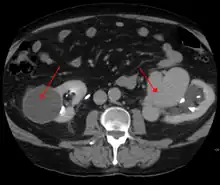

AVMs are diagnosed primarily by the following imaging methods:

- Computerized tomography (CT) scan is a noninvasive X-ray to view the anatomical structures within the brain to detect blood in or around the brain. A newer technology called CT angiography involves the injection of contrast into the blood stream to view the arteries of the brain. This type of test provides the best pictures of blood vessels through angiography and soft tissues through CT.

- Magnetic resonance imaging (MRI) scan is a noninvasive test, which uses a magnetic field and radio-frequency waves to give a detailed view of the soft tissues of the brain.

- Magnetic resonance angiography (MRA) – scans created using magnetic resonance imaging to specifically image the blood vessels and structures of the brain. A magnetic resonance angiogram can be an invasive procedure, involving the introduction of contrast dyes (e.g., gadolinium MR contrast agents) into the vasculature of a patient using a catheter inserted into an artery and passed through the blood vessels to the brain. Once the catheter is in place, the contrast dye is injected into the bloodstream and the MR images are taken. Additionally or alternatively, flow-dependent or other contrast-free magnetic resonance imaging techniques can be used to determine the location and other properties of the vasculature.